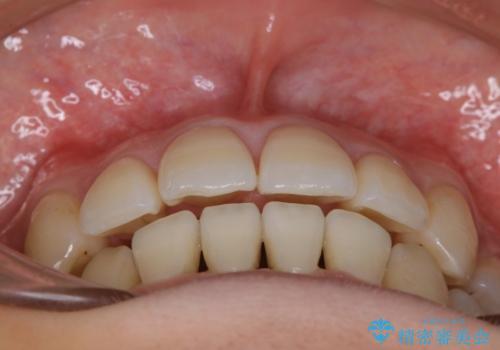

八重歯がスッキリ 抜歯ワイヤー矯正

- 以前からコンプレックスだった八重歯の治療を主訴にご来院されました。

叢生の度合いが重く、抜歯が必要なケース。八重歯の部分以外には大きな問題は認められなかったため、劇的変化が起こる治療でも比較的短期間で終了することができました。